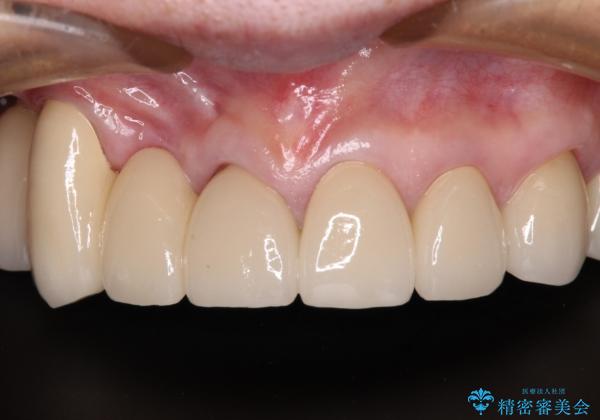

治療途中で放置してしまった前歯 オールセラミッククラウンによる補綴治療

- 前歯の部分矯正や仮歯に置き換えるなど、治療途中のまま放置してしまったとのことで来院された患者様です。

前歯部については抜歯が必要な歯を抜歯し、インプラントやブリッジなどにより補綴治療を行うこととしました。